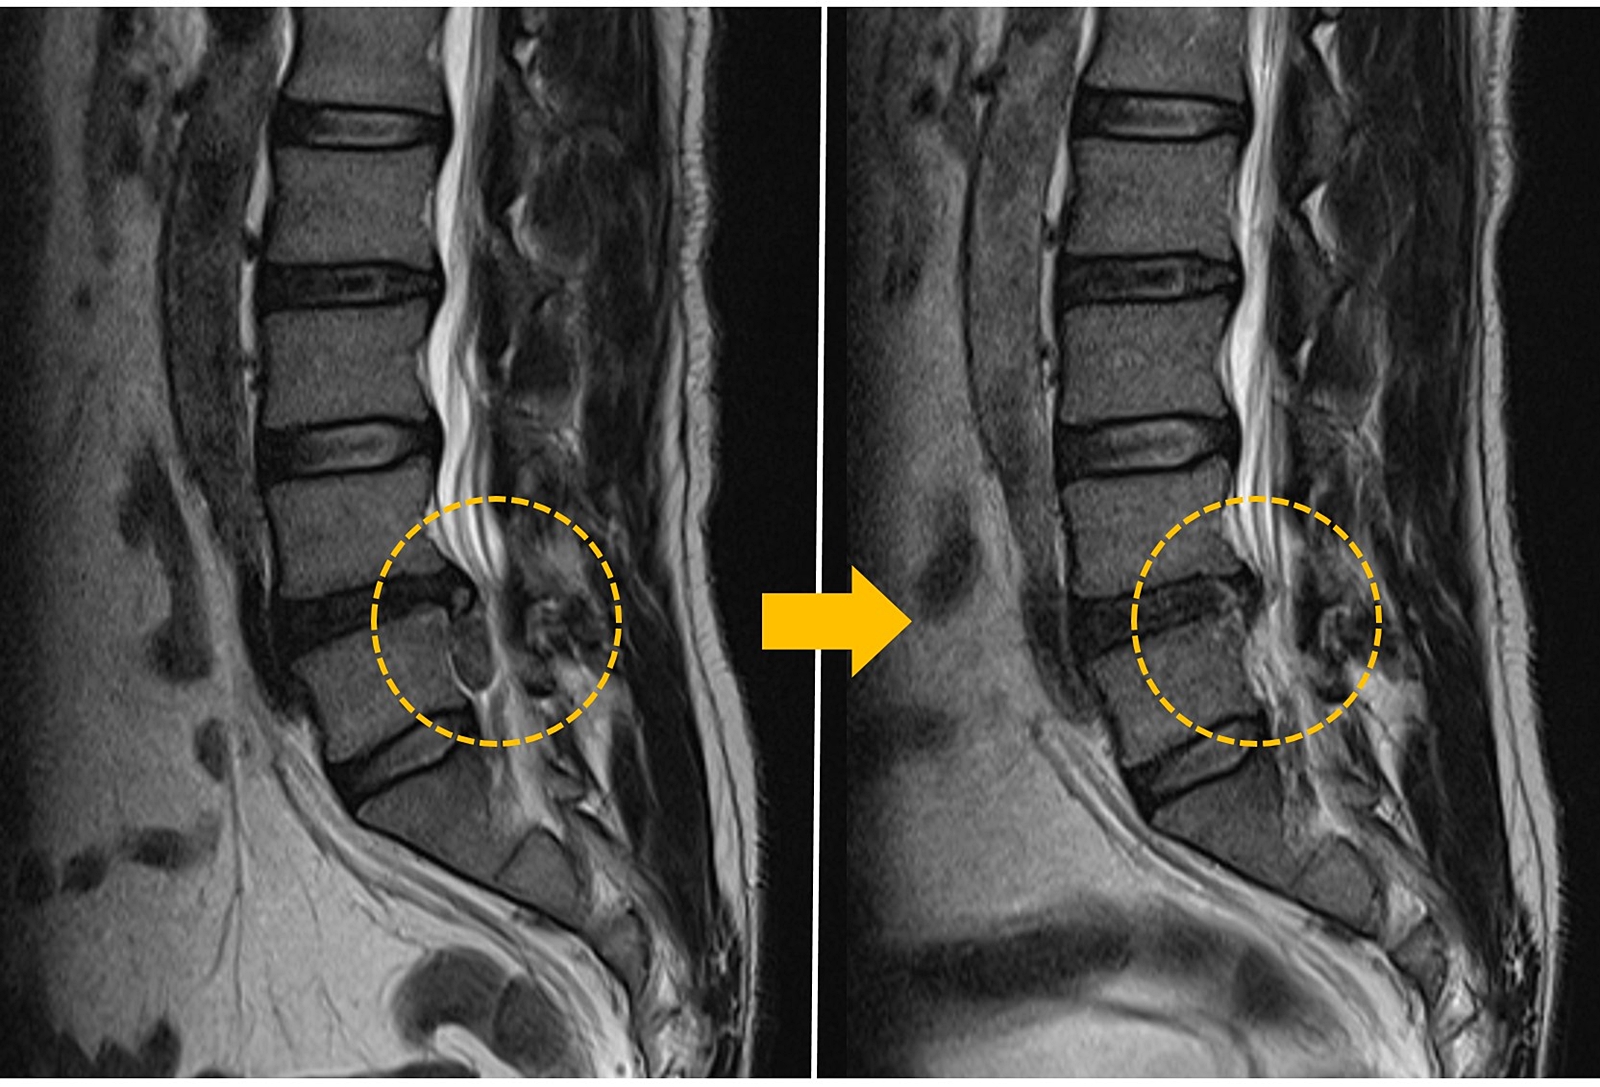

Spinal treatment that preserves normal tissue

Minimally Invasive Spine Surgery encompasses all forms of spine procedures, precisely targeting core lesions while minimizing damage to healthy tissues, thereby maximizing treatment effectiveness.

Busan Wooridul Spine Hospital specializes in minimally invasive spine surgeries and procedures that preserve normal tissue with minimal incisions. Our aim is to promote rapid recovery, ensure a quick return to daily activities, and prevent complications and aftereffects, helping patients achieve a pain-free, better quality of life.